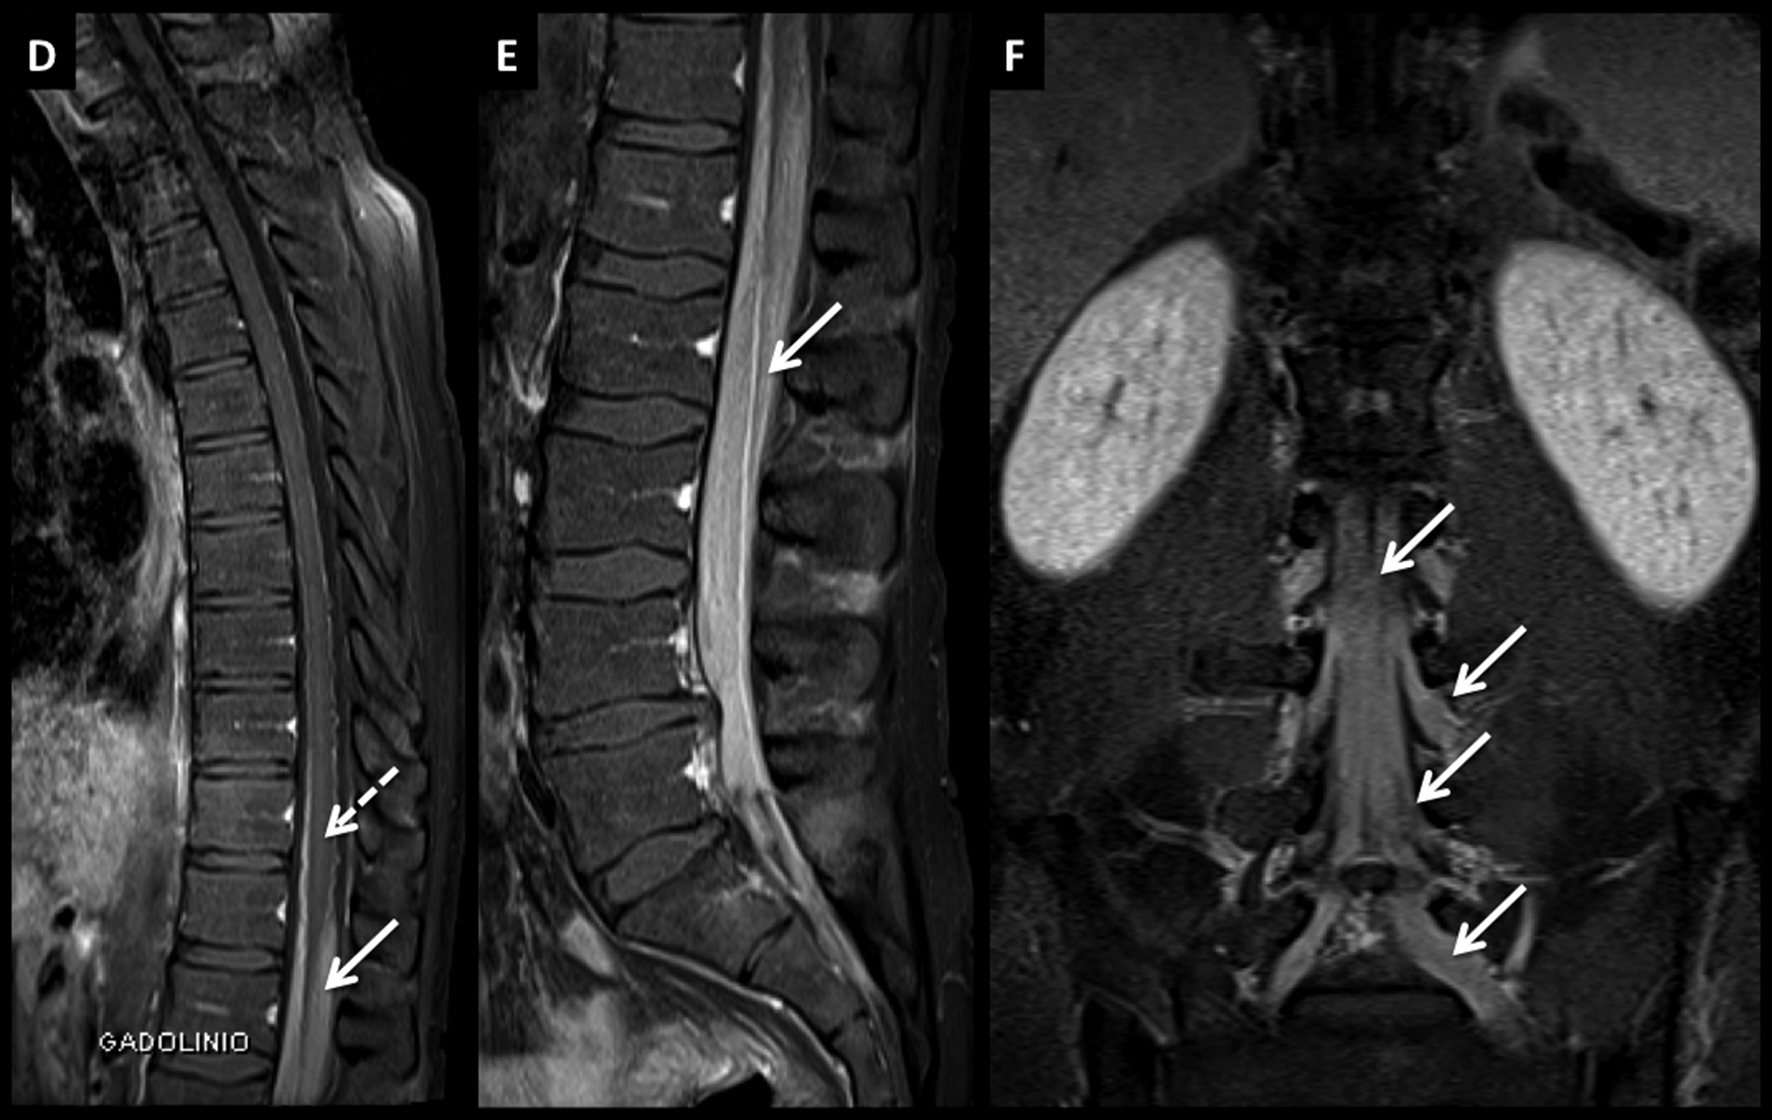

LNH, infiltración de cola de caballo, compromiso leptomeníngeo secundario.

Paciente joven con LNH y síndrome radicular asociado. En el estudio de estadificación se encuentra un patrón de infiltración de las raíces de la cola de caballo y se confirma el diagnóstico por estudio citológico del líquido céfalo raquídeo.

Este tipo de patrón se caracteriza por raíces nerviosas engrosadas que luego de administrar medio de contraste (D a F) presentan intenso realce.

El proceso infiltrativo rodea al cono medular (flecha discontínua) y puede contribuir a la clínica del paciente.